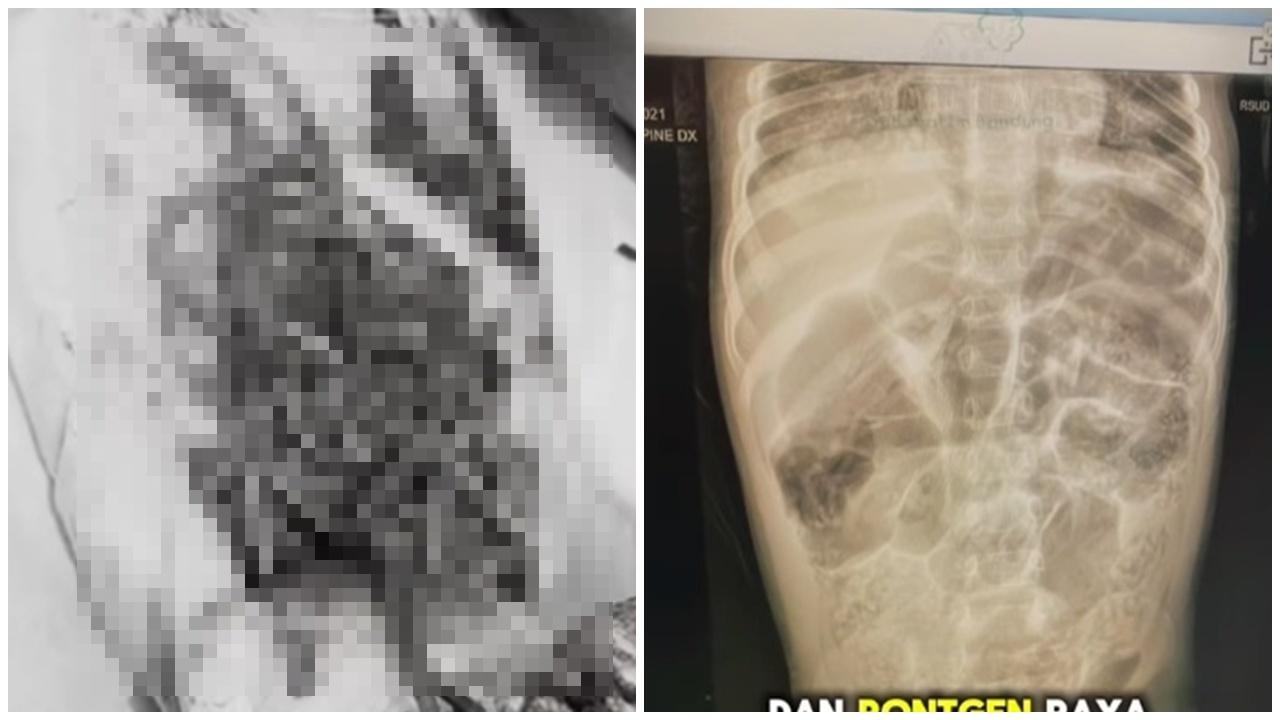

綜合報道,事發於上月13日,在西爪哇Kabandungan地區,女童Raya被送抵醫院前已失去意識。醫生指出,女童病情惡化且併發腦膜結核,最終回天乏術,7月22日宣告不治。值得關注的是,當地慈善機構Rumah Teduh也公開了女童病危的影片,畫面中能夠看見,女童鼻孔竟爬出一條15厘米的活蛔蟲;排泄物中的蛔蟲則超過1公斤,機構希望事件能提醒民眾關注飲食衞生。